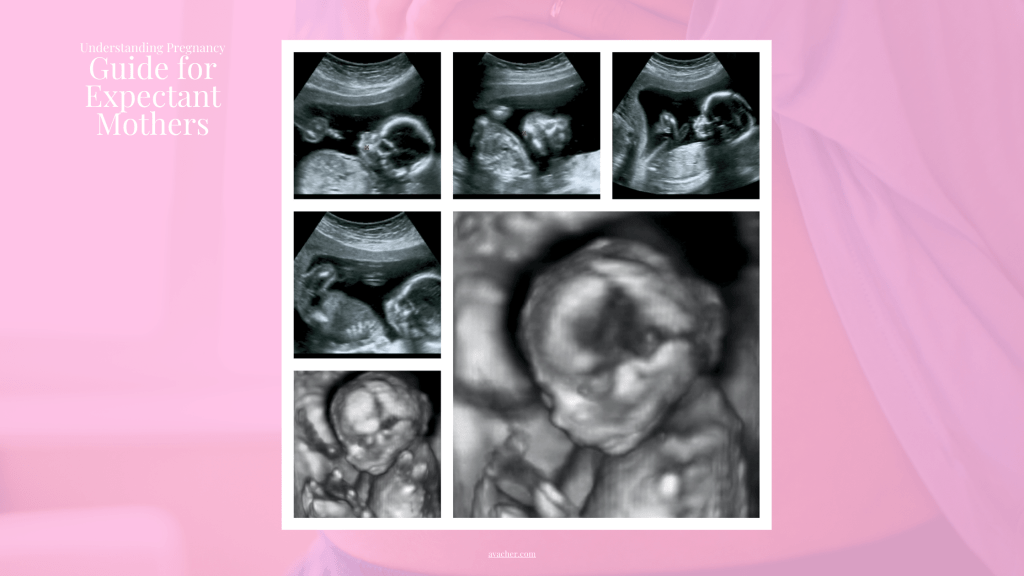

Your Baby’s Development: In this trimester, your baby will transform from a fertilized egg into a fully formed, albeit tiny, human! By the end of the first 12 weeks, your baby will have developed most of their organs and body parts.

Your Baby’s Development: During the second trimester, your baby is busy growing and becoming more active. By week 20, your baby will have developed unique fingerprints. They can yawn, stretch, and make facial expressions, even frown!

Your Baby’s Development: In the third trimester, your baby is essentially preparing for life outside the womb. They’ll continue to gain weight, their brain will grow rapidly, and they will start to open and close their eyes.